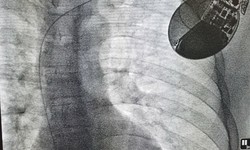

Camera bệnh viện - 13/12/2019 07:46SKĐS - Trung tâm Tim mạch thuộc BVĐK tỉnh Phú Thọ vừa thực hiện cấy máy phá rung cho người bệnh bị xoắn đỉnh, rung thất. Anh Trần Văn S. (43 tuổi, trú tại TP. Việt Trì - tỉnh Phú Thọ) có biểu hiện hồi hộp, tức ngực và ngất, được đưa vào Bệnh viện đa khoa tỉnh Phú Thọ.